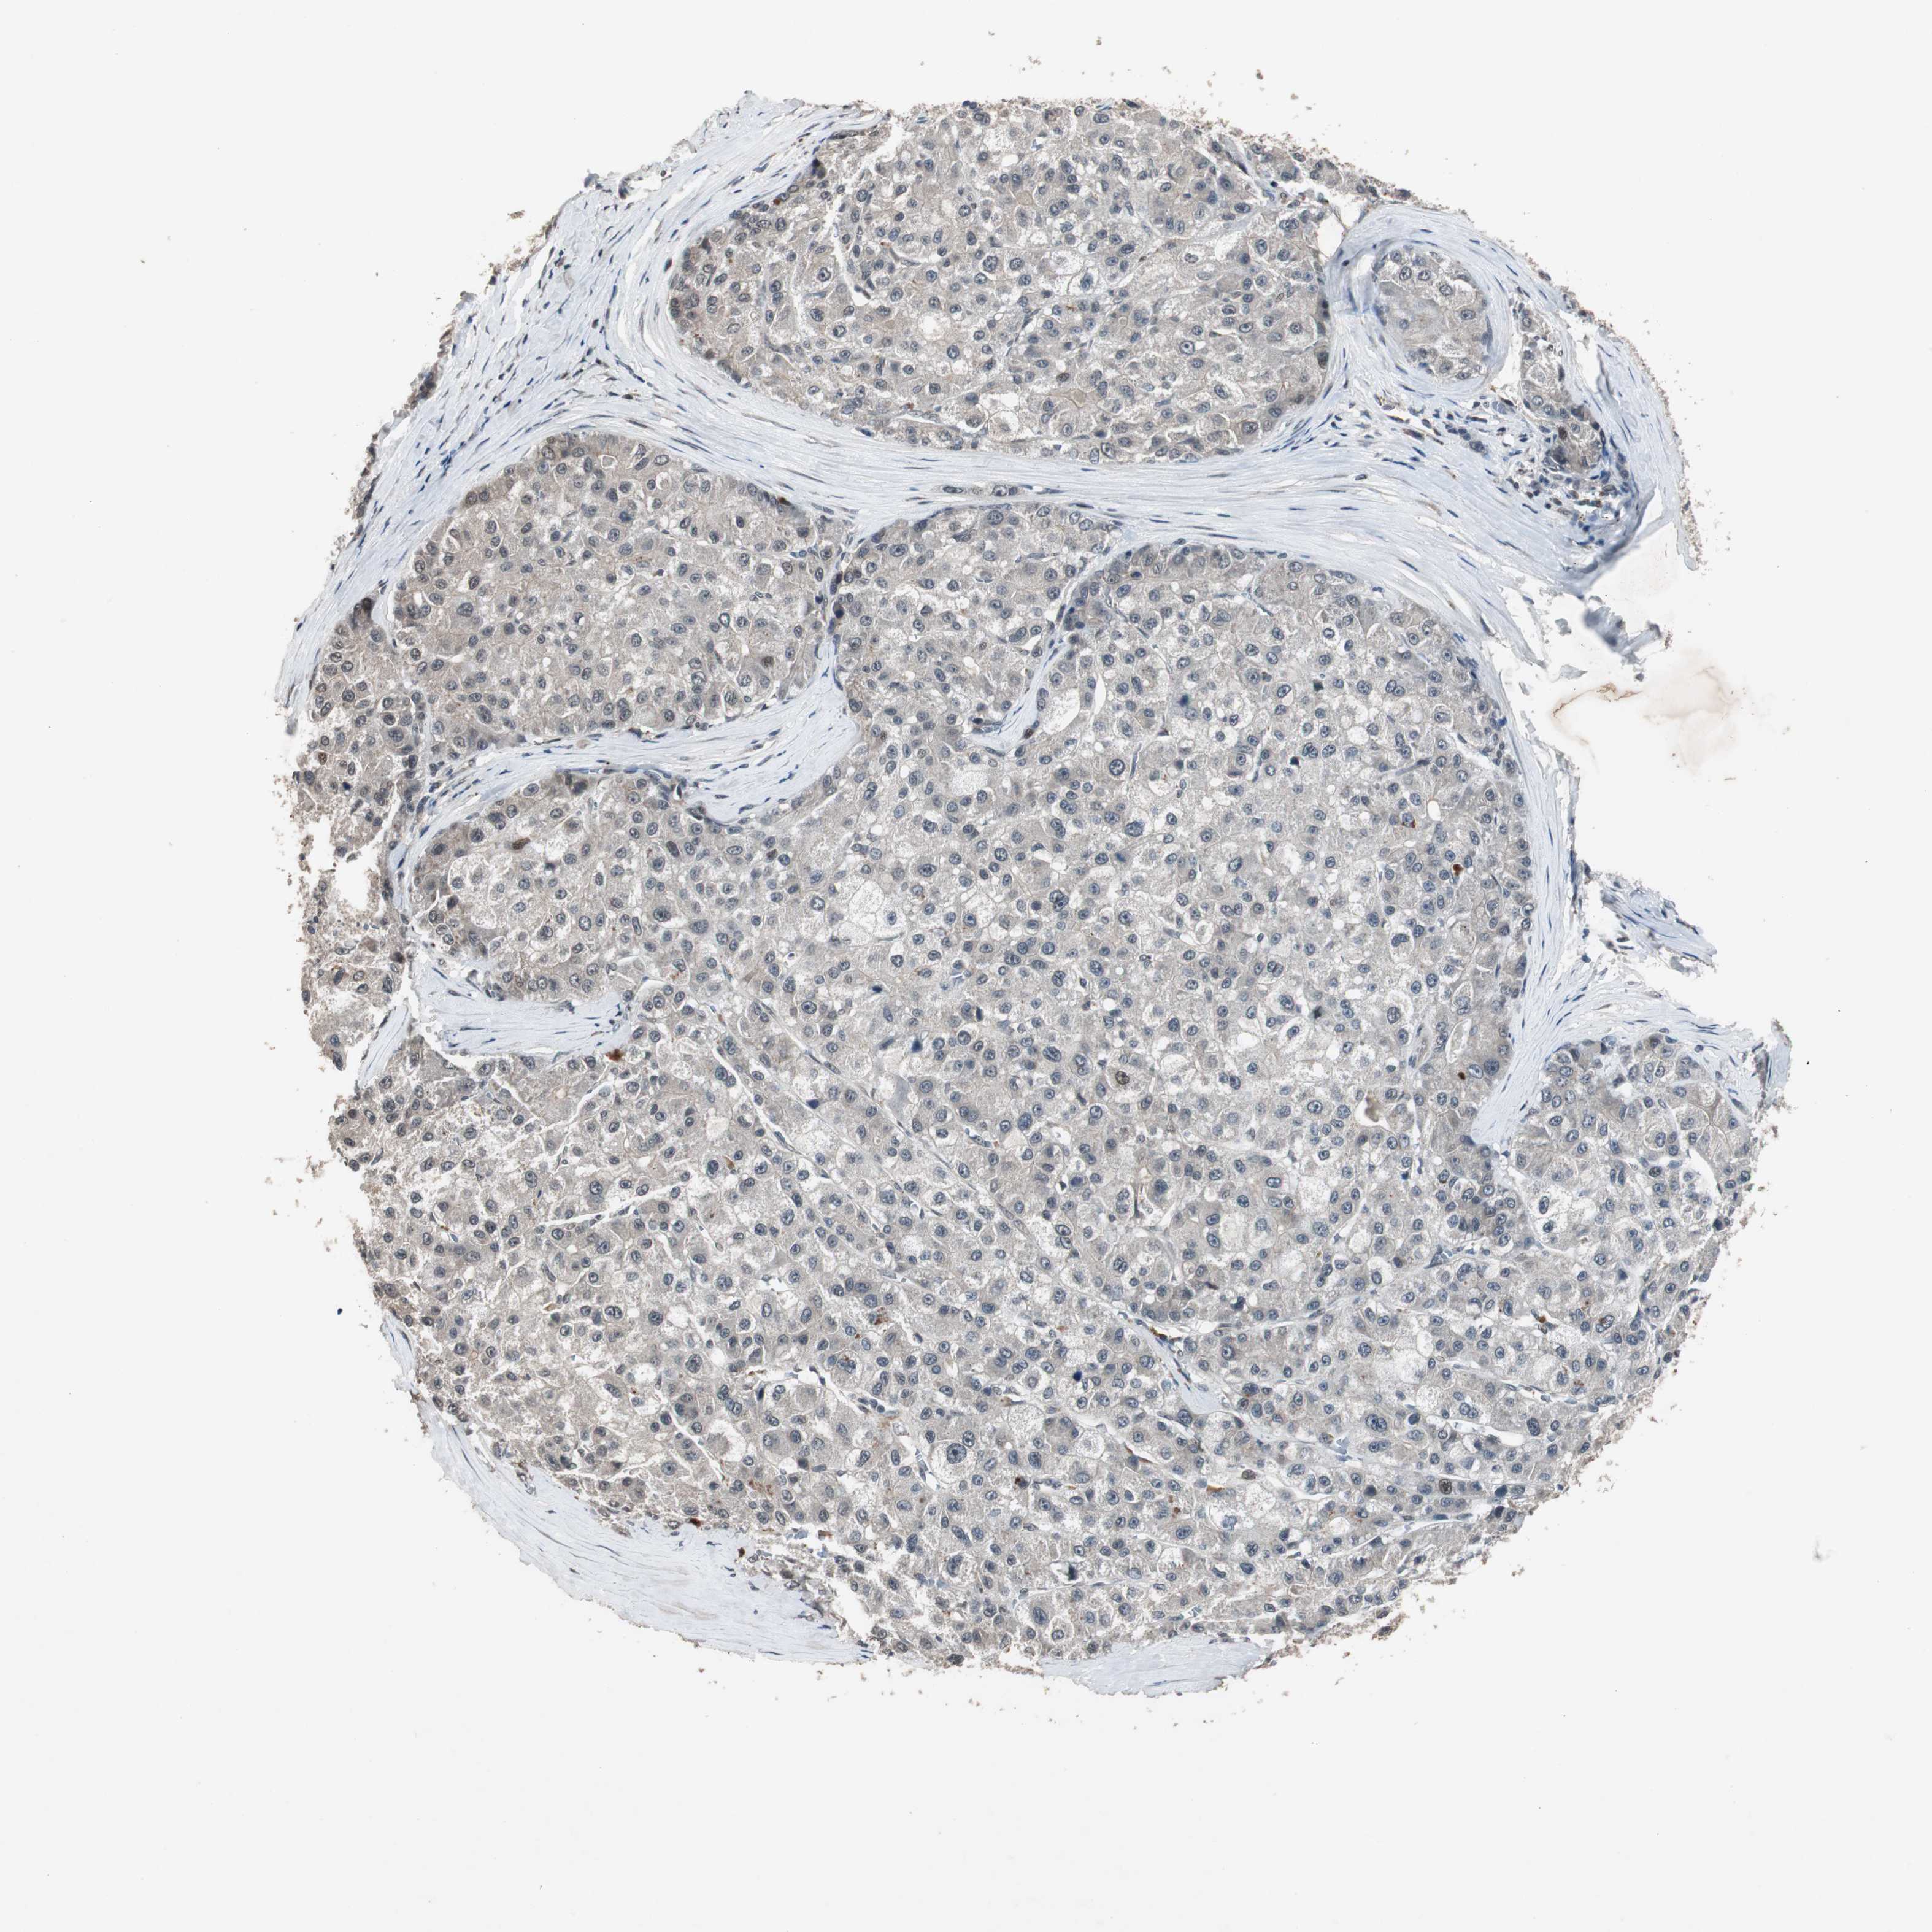

LIVER CANCER - Protein expressioni

A mouse-over function shows sample information and annotation data. Click on an image to view it in a full screen mode. Samples can be filtered based on level of antibody staining by selecting one or several of the following categories: high, medium, low and not detected. The assay and annotation is described here.

Note that samples used for immunohistochemistry by the Human Protein Atlas do not correspond to samples in the TCGA dataset.

Antibody stainingi

Antibody staining in the annotated cell types in the current human tissue is reported as not detected, low, medium, or high, based on conventional immunohistochemistry profiling in selected tissues. This score is based on the combination of the staining intensity and fraction of stained cells.

Each image is clickable and will lead to virtual microscopy that enables deeper exploration of all samples and also displays staining intensity scores, fraction scores and subcellular localization as well as patient and tissue information for each sample.

Antibody HPA007005

Staining

High

Medium

Low

Not detected

Intensity

Strong

Moderate

Weak

Negative

Quantity

>75%

75%-25%

<25%

None

Location

Nuclear

Cytoplasmic/membranous

Cytoplasmic/membranous,nuclear

Cholangiocarcinoma

Carcinoma, Hepatocellular, NOS